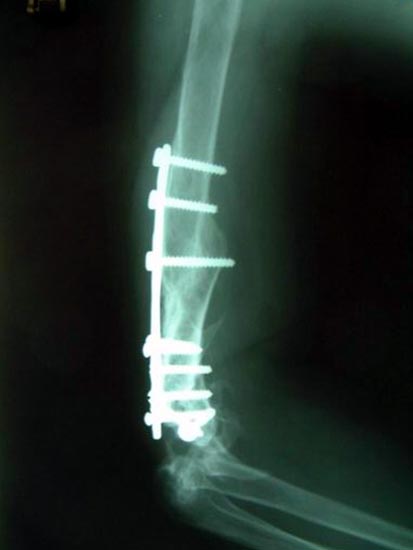

病例四、

肱骨骨不连的骨断端多有硬化而骨干骨质疏松、遗留有以往手术的钢板、

钉孔,骨吸收骨干变细有严重骨缺损,治疗困难较大。

带锁髓内钉内固定,解决骨质疏松、骨干变细和骨缺损等情况

下的固定问题,进行复合骨髓细胞的植骨,促进骨折愈合